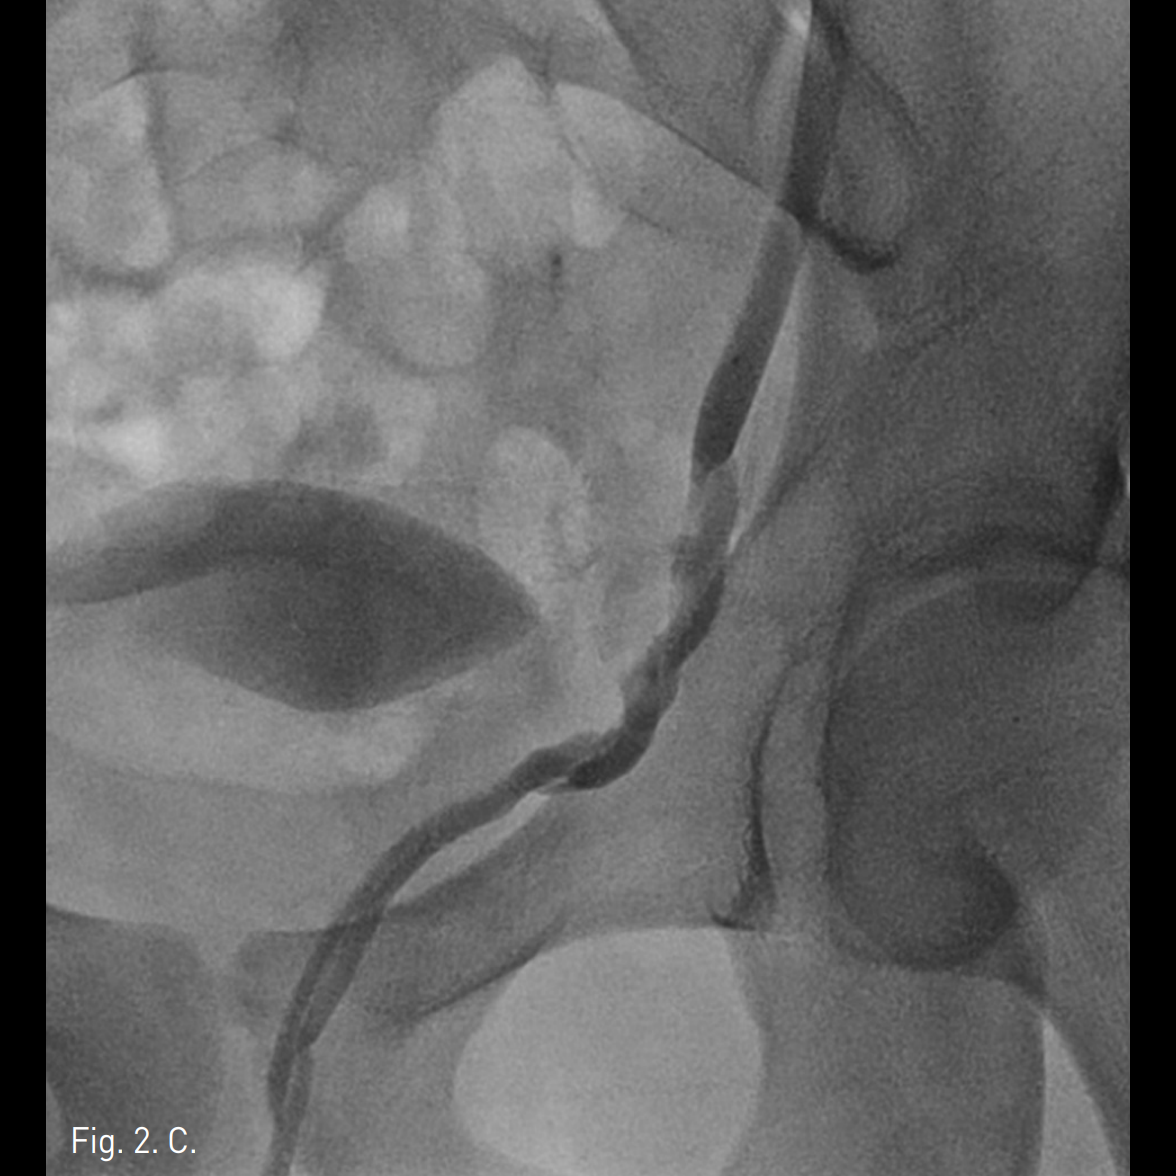

우측 상박을 tourniquet으로 묶은 후 초음파 유도 하에 우측 basilic vein을 minipuncture set을 이용해 천자하여 4Fr Cobra catheter (100cm)를 좌측 신정맥에 위치시킨 후 table tilting을 하여 조영제를 넣었을 때 좌측 spermatic vein.으로의 역류가 관찰되며 L3 level에서 retroperitoneum으로 통하는 venous tributary가 있으며 main tributary는 좌측 pampiniform plexus로 역류되는 소견이 보임(Fig. 2A, 2B). Microcatheter (Renegade, Boston Scientific, Watertown, MA)를 이용하여 보다 자세한 정맥조영을 얻었을 때 inguinal canal level에서 두 개의 정맥이 관찰됨(Fig. 2C). Subinguinal level에서 3개의 microcils (2~3mm ; micronester, Cook, Bloomington, IN)를 이용하여 색전술을 시행하였음 (Fig. 2D). 이어서 환자의 왼쪽 손가락을 이용해 inguinal level을 압박하게 하고 조영제를 주입했을 때 고환으로의 조영제 흐름이 차단된 것을 확인한 후(Fig. 2E), foam sclerotherapy (2mL of 3% STS [sodium tetradecyl sulfate, Thrombojet] + 3mL of air) 5mL를 Cobra catheter를 통해 시행함. 근위부 spermatic vein에 3개의 coils (6mm Nester coils)로 색전술을 시행함. 최종 좌측 신정맥조영술에서 spermatic vein이 조영되지 않음(Fig. 2F).

Fig. 2

C, D. Selective spermatic venograms show two spermatic veins at spermatic cord levd. Three microcoils were deployed in one of the two veins.